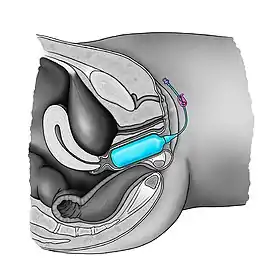

Vaginal dilators, also called vaginal stents or vaginal expanders, can be inflatable and are used during surgeries.[5][6] Vaginal stents are routinely used in postoperative care for transgender patients who have undergone vaginoplasty as part of gender confirmation surgery. They are also used for various conditions, such as vaginal agenesis.[7] The vaginal expander is used immediately after surgery to keep the passage from collapsing, and regularly thereafter to maintain the viability of the neovagina. Frequency of use requirements decrease over time, but remains obligatory lifelong.[8][9]

With solid vaginal dilators, the patient starts with the smallest dilator size, then gradually increasing until the largest dilator size is reached. This practice can be accompanied by breathing exercises in order to relax the pelvic floor muscles. Dilation acts should not cause pain or bleeding.[10] Dilatation with rigid dilators must be done carefully as vaginal perforation and urethral injury may occur.[11][12] There is no consensus on the frequency and duration of using vaginal dilators.[13] In case of vaginal expanders, the therapist or the patient introduces the deflated balloon into the vagina and then inflates it gently until the required diameter is obtained.[7]